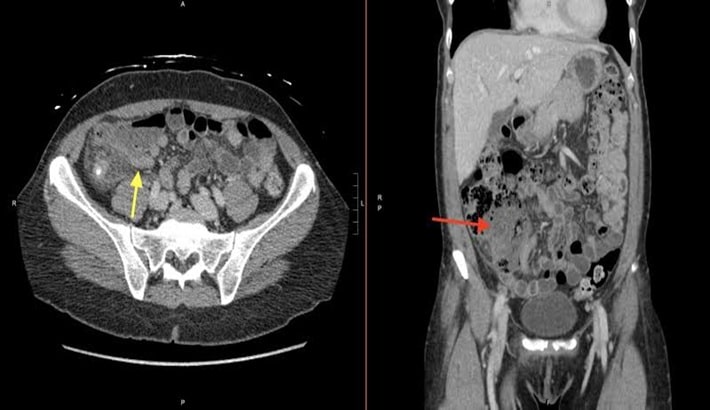

نقش سی تی اسکن شکم در تشخیص تومورها و سرطانها

سی تی اسکن شکم تنها برای بررسی درد یا التهاب نیست، بلکه در شناسایی بسیاری از تومورها نیز نقش حیاتی دارد.

شناسایی تومورهای دستگاه گوارش

تومورهای روده، معده یا کبد با استفاده از سی تی اسکن شکم در مراحل اولیه شناسایی میشوند. دقت بالای این روش باعث میشود پزشک بتواند محل دقیق توده و میزان درگیری بافتها را تشخیص دهد.

بررسی گسترش متاستاز در لگن و نواحی اطراف

در مواردی که بیمار دچار سرطانهای پیشرفته است؛ سی تی اسکن شکم و لگن بدون تزریق برای بررسی گسترش سلولهای سرطانی در اندامهای اطراف بهکار میرود. مرکز تابا در چنین مواردی از تصاویر سهبعدی و بازسازی دیجیتالی برای ارزیابی کامل وضعیت بیمار استفاده میکند.

سی تی اسکن شکم برای تشخیص بیماریهای مشابه

در بسیاری از موارد، درد پایین شکم ممکن است به دلایل دیگری مانند عفونت مثانه، کیست تخمدان یا مشکلات گوارشی باشد. سی تی اسکن شکم و لگن به پزشک کمک میکند این بیماریها را از هم تشخیص دهد و علت اصلی درد را مشخص کند. این دقت در تشخیص، از درمانهای غیرضروری یا اشتباه جلوگیری میکند.